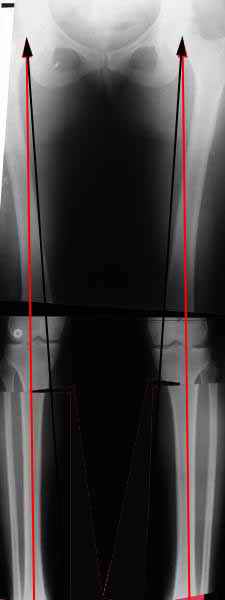

AC> Вот, с учетом и без учета, и на разных уровнях...

AC> Саша Артемьев, может, для данного случая свой вариант нарисуешь?

Из приведнной схемы не совсеим понял что означают разноцветные линии.

И зачем латерализация периферического фрагмента. Я всегда делаю медиализацию. См схему. И для данного случая медиализация подходит как нельзя лучше.

a> Из приведнной схемы не совсеим понял что означают разноцветные линии.

Черные - это нынешняя механическая ось. Красные - это планируемая правильная ось.

a> И зачем латерализация периферического фрагмента.

;-) Читайте Палея. Стр. 114-115.

a> Я всегда делаю медиализацию. См схему. И для данного случая

Медиализация - это чисто эстетический прием, как я понимаю. Поскольку если делать остеотомию ниже вершины деформации, для восстановления оси надо делать смещение по ширине, в данном случае как раз латерализацию.

А вот на схемке без осей - там на разных уровнях (который правильнее?) устранение варуса чисто открытым клином без медиализации-латерализации. Если как-то так сделать - этого недостаточно будет?